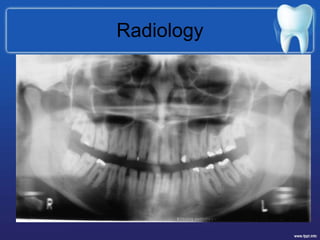

Radiology

• Picket fence appearance

• Spacing

• Thin enamel

• Hypo radiodensity of enamel

• Skeletal problems

Radiology • Picket fenceappearance • Spacing • Thin enamel • Hypo radiodensity of enamel • Skeletal problems